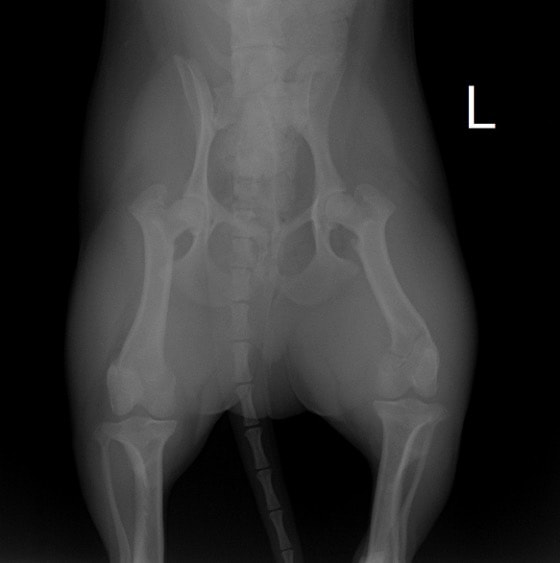

症例:交通事故による椎体脱臼

柴犬:9歳、避妊雌

交通事故直後、胸腰部に激しい疼痛、両後肢に完全麻痺を認め、シェフシェリントン徴候を呈していました。レントゲン検査において、第11-12胸椎間の脱臼が認められました。

脊髄の減圧、脊柱管の再構築・安定化を目的に、片側椎弓切除術およびMatrixMANDIBLE Plateによる椎体固定を実施しました。

隣接椎体を架橋するようにプレートを設置しました。

術後レントゲン写真